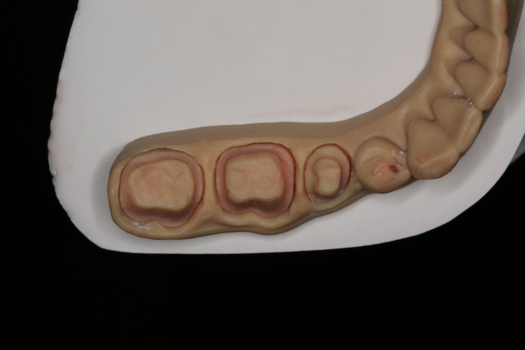

Case 1. Digital Impression and Fabrication of Crowns: Natural Teeth

After completing an initial diagnostic appointment, a patient accepted three single-unit full-contour zirconia crowns that were milled from the digital impression and cut back for porcelain application. The application by a technician is analog dentistry. The ability of a dental laboratory to scan an analog crown-and-bridge impression is called converting an analog impression to a digital impression. The workflow after the conversion has become digitized. A dental model is virtually created with computer software, and a full crown proposal is fabricated for inspection virtually before the crown is milled (Figure 2). Due to the color of the digitized impression, the margins of the crown preparations are more easily and rapidly identified. The laboratory will also 3D print a working model, which will be used to develop the morphology of the final restoration by hand placement of porcelain (Figure 3). The decision to prescribe a full contour zirconia crown with cutback for porcelain application or complete full contour zirconia crowns lies solely on the attending dentist.9 A discussion with the patient before preparation of the teeth is imperative. After the discussion, the patient requested the zirconia copings with cutback and porcelain application for the posterior crowns (Figure 4 and Figure 5).

Fig 3. 3D-printed model.

Figure 3

Fig 4. Zirconia with cutback for porcelain application.

Figure 4

Fig 5. Occlusal view of completed zirconia with porcelain application on teeth Nos. 29, 30, and 31.

Figure 5